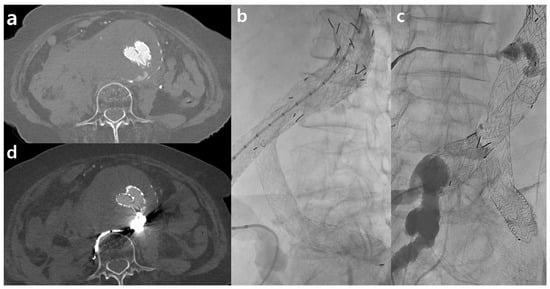

For the estimation of vessel sharpness (VS) [14], a line profile perpendicular to the proximal SMA within 2 cm from the SMA os was generated using FIJI’s [15] “Line Profile” function (Figure 1). The slope of the regression line for the anterior vessel border (sloperise) and the posterior vessel border (slopefall) was calculated with Excel’s built-in “slope function”. The mean of the sloperise and the absolute value of the slopefall were calculated to report quantitative numbers for VS. The proximal SMA was chosen for its good delineation due to the surrounding mesenteric fat, making it suitable for evaluating vessel sharpness. All patients were measured with a window width of 400 HU and a window level of 60 HU in the arterial phase.

Vessel sharpness = mean (sloperise + abs(slopefall))

The Full-Width at Half Maximum (FWHM) edge criterion is a quantitative metric that provides a reliable and robust estimation of a vessel lumen’s edge by defining the boundary at a 50% intensity level between the maximum (lumen) and minimum (tissue). This criterion allows for accurate detection of the vessel lumen and derivation of vessel parameters such as diameter or cross-sectional area [16,17]. To generate FWHM values, the line profile from the proximal SMA computed with FIJI’s “Line Profile” function was used. The length (in millimeters) at the half maximum of the line profile curve was measured to reveal the FWHM value.

Figure 1. Representative example of a thoraco-abdominal aorta computed tomography angiography (a) (in this case arterial phase scan) used for quantitative image quality analysis. Based on a line profile perpendicular (red line) to the proximal SMA, vessel sharpness and FWHM values were derived (b). Representative example of ROI placement on source images for signal-to-noise ratio (SNR) and contrast-to-noise ratio (CNR) measurements (c).